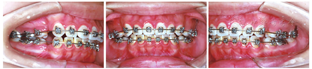

恒牙列,口内未见18、28、38、48;上下颌牙弓卵圆形,上下弓形左右基本匹配对称;上中线与面中线基本对正,下中线右偏1 mm;左侧磨牙、尖牙中性关系,右侧磨牙、尖牙完全远中关系;前牙覆

1 mm,覆盖3 mm;上下颌牙列轻度拥挤(上颌4 mm,下颌2 mm);17、47锁

(图1)。